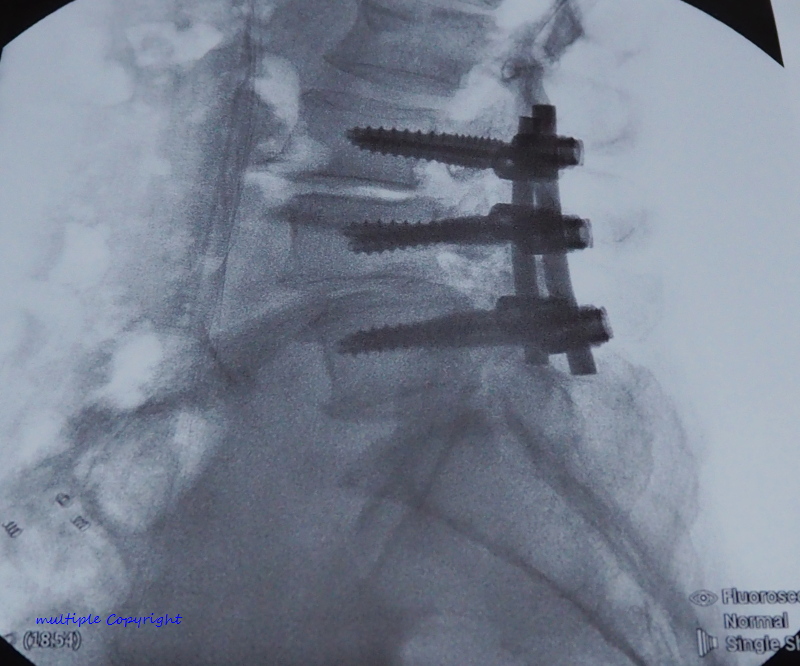

3. อวัยวะล่าสุด ที่ถูกเปลี่ยนก็คือ แกนกลาง ลำตัว Titanium ที่เป็นโลหะเบา แต่แข็งแกร่งพอๆกับเหล็กกล้า ทนทานต่อการกัดกร่อน ทนต่อความร้อนสูงและแรงเสียดสีเวลาใช้งานหนัก และยังไม่เป็น สื่อแม่เหล็ก สามารถผ่าน เครื่องสแกนทุกชนิดได้ ... เปิดตัว Project Titanium มานี่ ยังกับหนัง คนเหล็ก 3กำเนิดใหม่ เครื่องจักรสังหาร เลยนะครับ5555 เพื่อนๆแฟนคลับ คงทราบข่าว ว่า อาจารย์เต๊ะ ไป ผ่าตัด กระดูกสันหลัง มากันแล้วนะครับ มาครับมา เตรียมปูเสื่อ ข้าวโพดคั่ว ส้มตำปูปลาร้ามา กันเลย เดี๋ยว อาจารย์เต๊ะ จะเล่าให้ฟังนะครับ ....

.... พูดถึงการผ่าตัดครั้งนี้นี่ ฟังจากปากพี่สาวที่ คุณหมอ บอก มาเล่าให้ฟังว่า เคส อาจารย์เต๊ะ ค่อนข้างยากและซับซ้อน เพราะกระดูกทั้งเคลื่อน ทั้งกดทับเส้นประสาทด้วย ต้องใช้หมอ เฉพาะทาง ถึง 2 คน มาช่วยกันผ่า โชคดี คุณหมอมี พี่น้องฝาแฝด เป็นหมอกระดูกเหมือนกันด้วย เลยได้มาช่วยผ่าด้วยกัน แล้วก้จริงๆ คุณหมอนี่เชี่ยวชาญการผ่าโดยใช้ หุ่นยนต์มาก แต่ เคส อาจารย์เต๊ะ ยากเกิ้นนน ต้องผ่าแบบธรรมดาแผลใหญ่

แต่ถึงจะยากแค่ไหน ด้วยประสบการณ์คุณหมอ ก็สามารถผ่าได้สำเร็จ เรียบร้อยดี